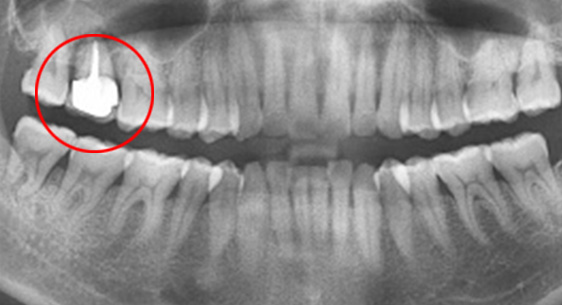

치아 배열이 가지런하게 되었고 제거된 임플란트 공간은 앞니의 후방이동과 어금니들의 전방이동으로 잘 폐쇄되어 본인의 치아를 최대한 보존하며

교정적으로도 만족할 수 있는 결과를 획득하여 유지하고 있습니다.